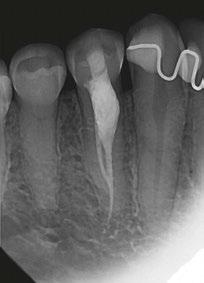

Figure 1: CBCT scan of the tooth demonstrating the radiolucent lesion surrounding the DI and extending to the apex of the central incisor Figures 2A-2D: 2A. Periapical radiograph of the dens. 2B. Hedstrom file in the invagination. 2C. The obturated enamel lining of the invagination with BC putty. 2D. Healing of the periapical lesion in the 1-year follow-up

int the C-shaped main canal. 3D.The obturated enamel of lined canals with Biodentine. The radiopacity is similar to that of dentin. 3E. Healing of the periapical lesion in the 3-year follow-up and continued root formation